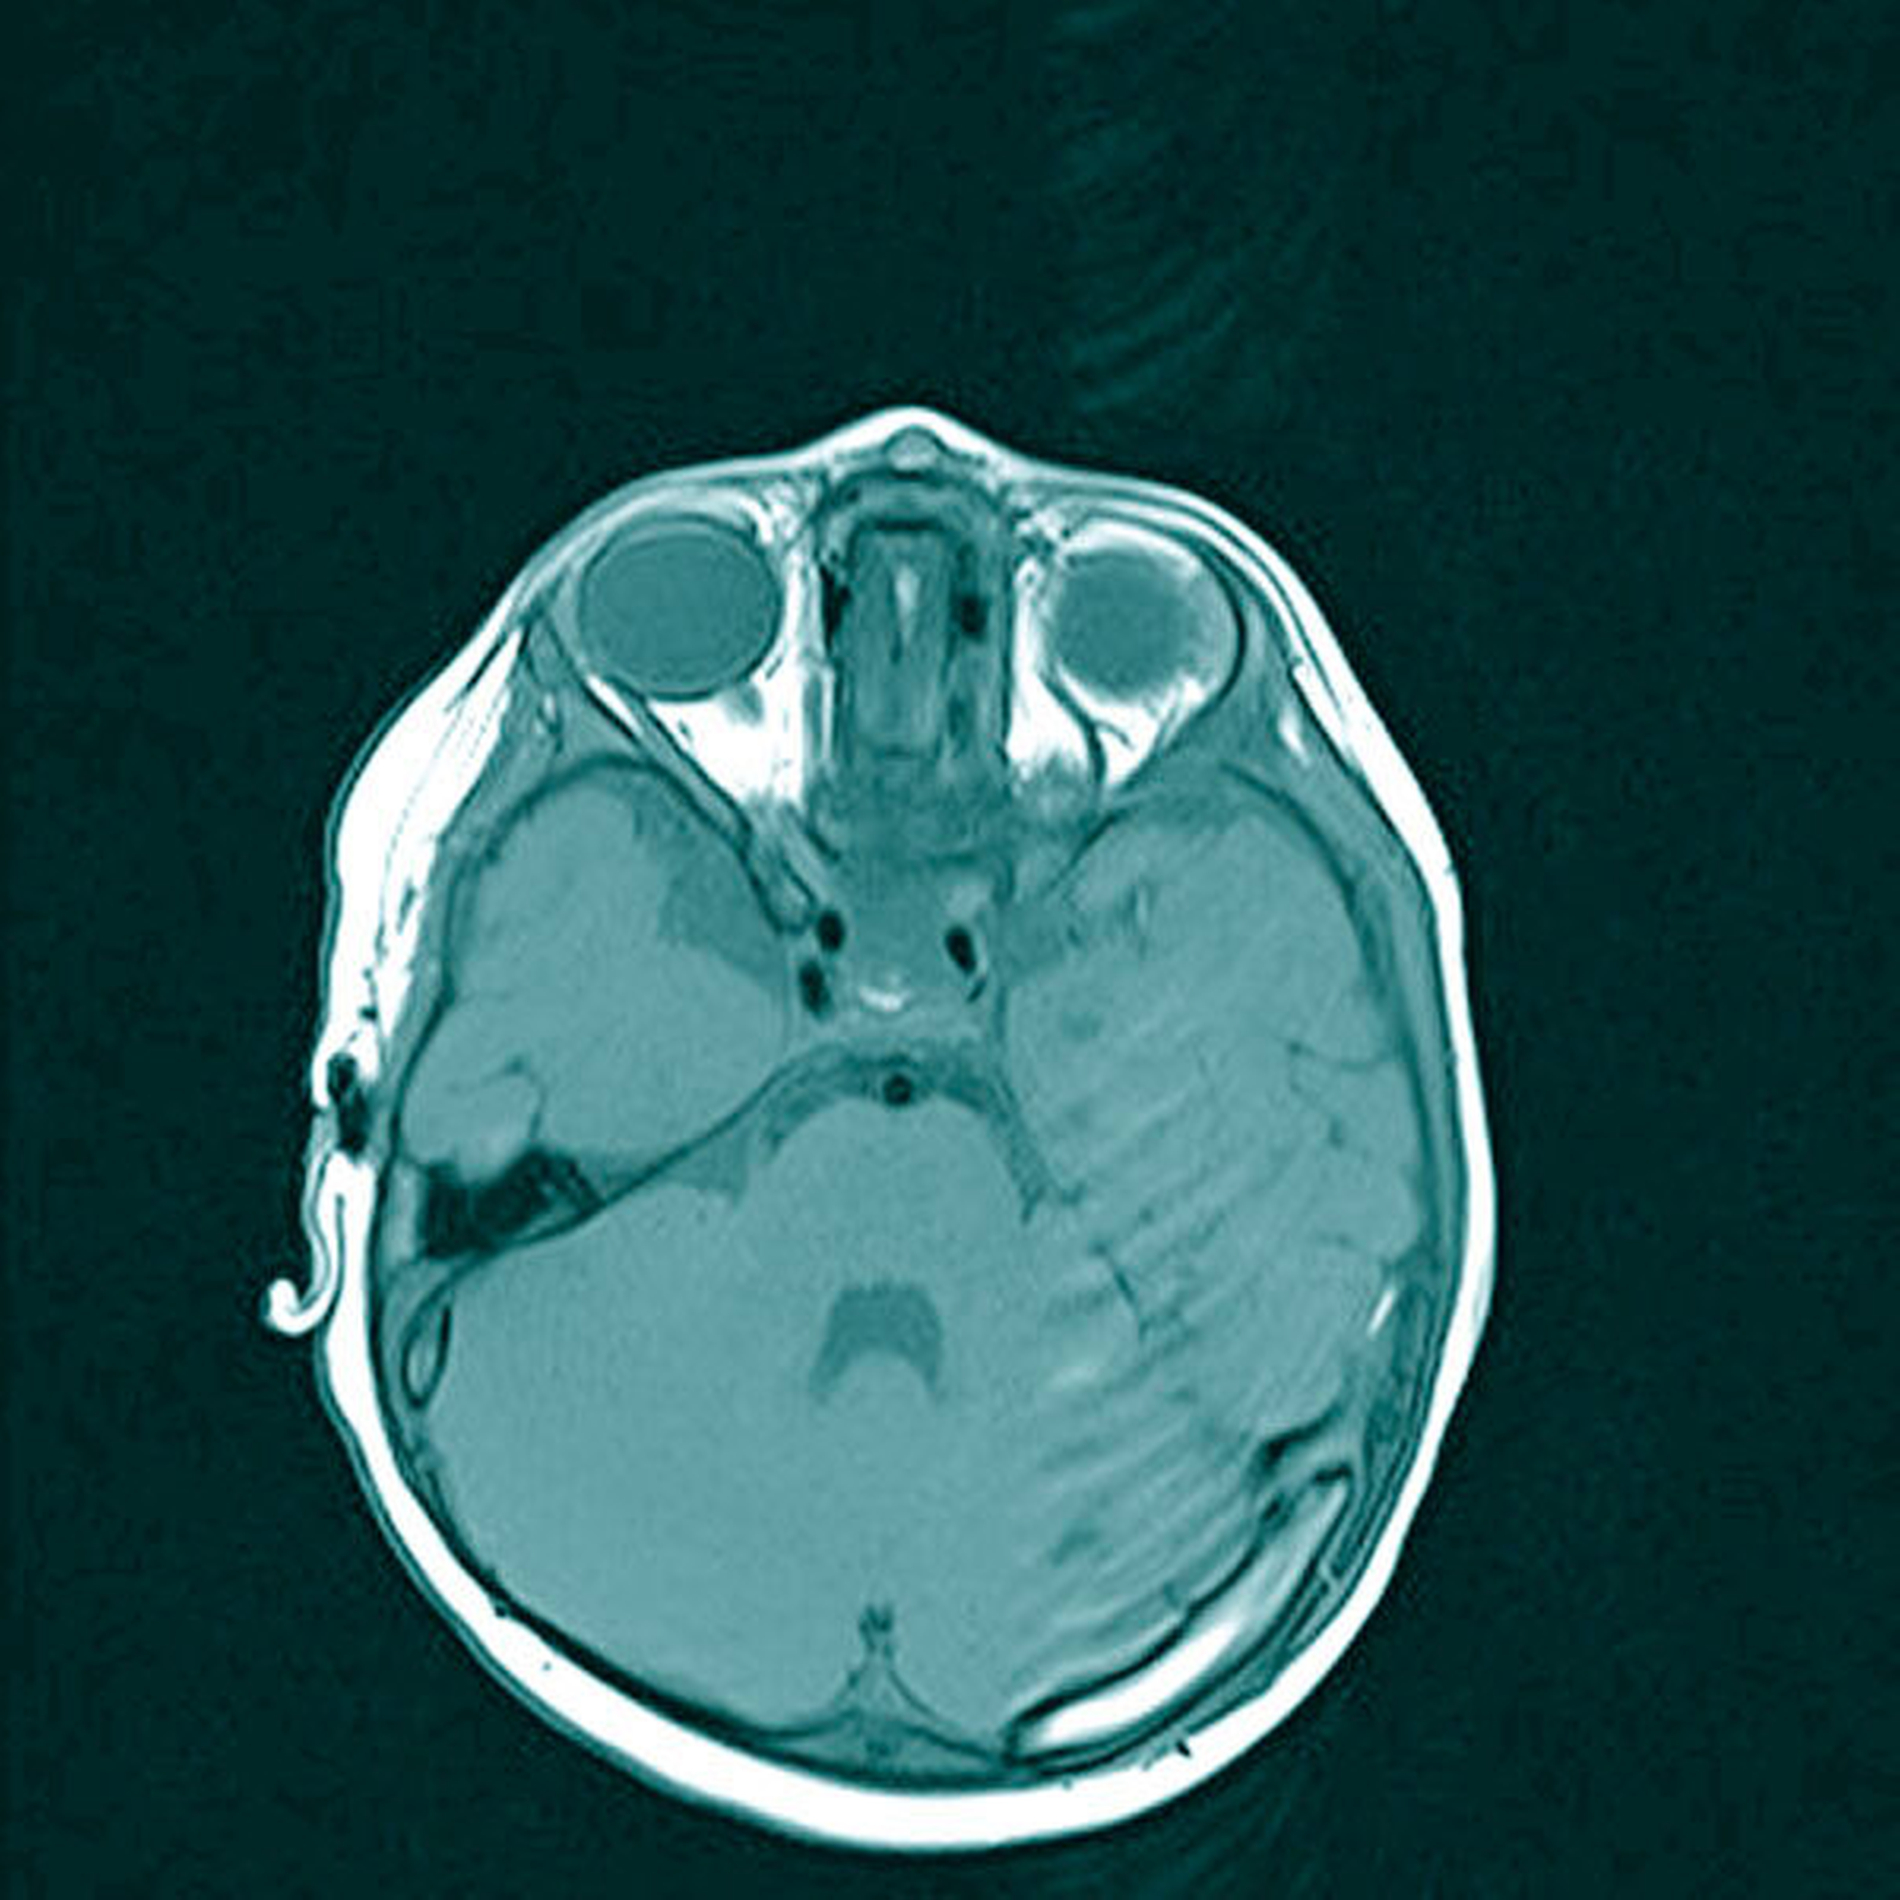

Im MRT bestätigte sich das Vorliegen einer umschrieben-bekapselten, rundlichen Formation median an der Glabella. Der Tumor war inhomogen hypointens in der T1- und hyperintens in der T2-Wichtung (Abbildungen 2 und 3). Des Weiteren stellte sich eine leicht imprimierte Tabula externa der angrenzenden Kalotte ohne Nachweis einer intrakraniellen Ausdehnung dar (Abbildung 4). Somit erhärtete sich der Verdacht auf Vorliegen einer Epidermoid- beziehungsweise einer Dermoidzyste und nach Rücksprache mit den Eltern erfolgte die chirurgische Entfernung.